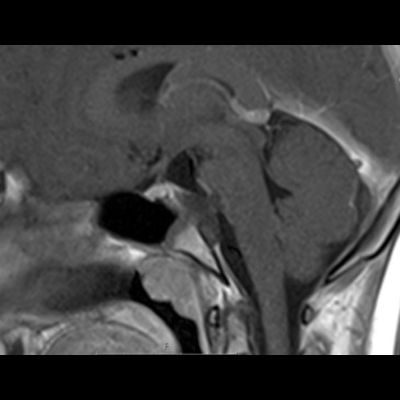

12 yaş, E

Dirençli baş ağrısı

Retroklival, Prepontin, İntradural, Saplı benign Kitle Ecchordosis physaliphora

Ecchordosis physaliphora

Ecchordosis physaliphora

Ecchordosis physaliphora